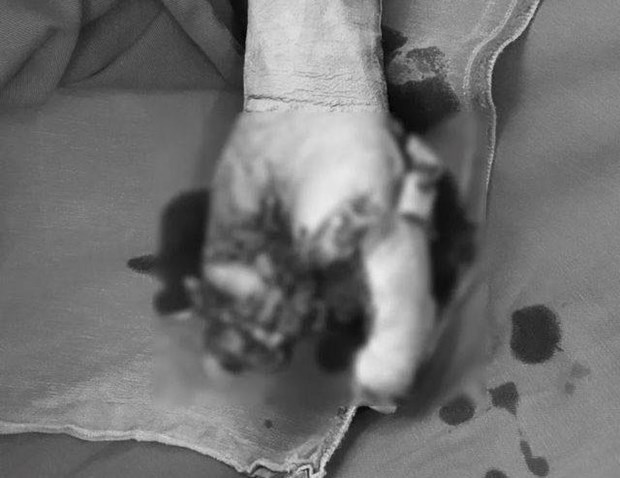

Bàn tay của bệnh nhân bị dập nát do điện thoại phát nổ

Bệnh nhân bị dập nát bàn tay, vết thương mắt 2 bên, vết thương xuyên nhãn cầu có dị vật nội nhãn.

Bệnh nhân được chỉ định mổ cấp cứu, cắt cụt 1/3 dưới cẳng tay.